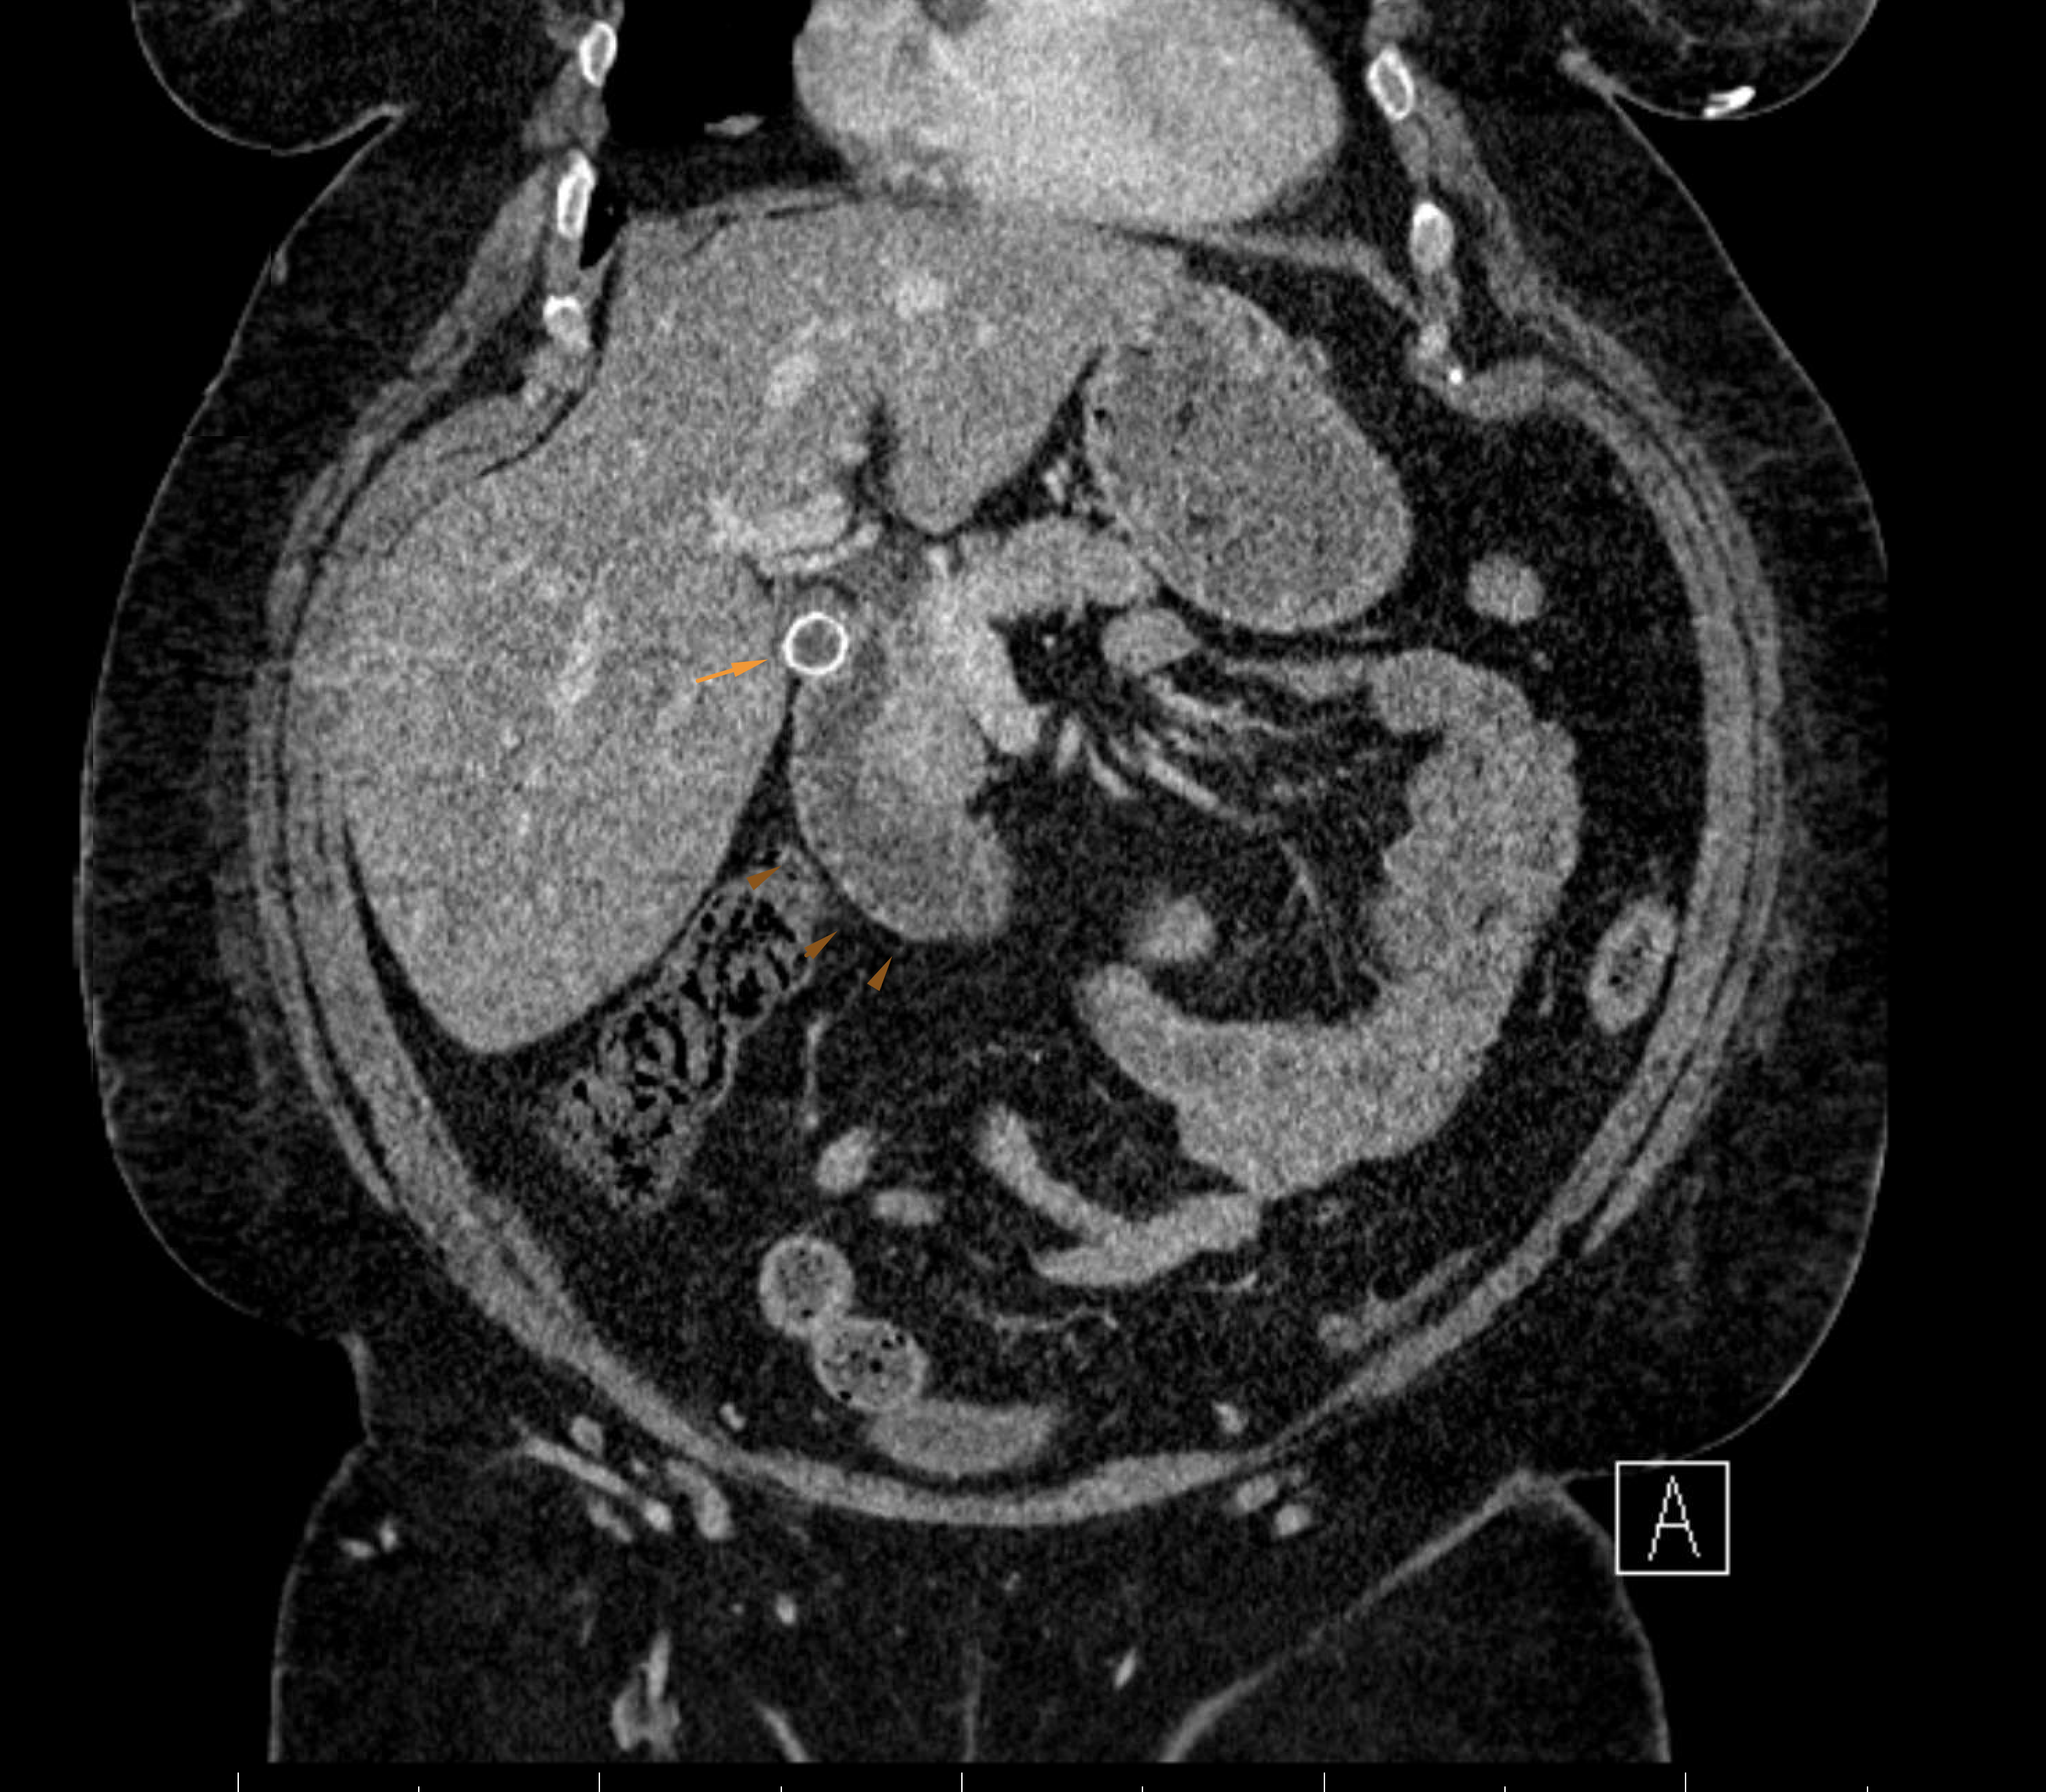

Age: 54

Sex: Female

Indication: Nausea, vomiting

Radiotracer: Tc99m Mebrofenin

Sample ReportFindings consistent with acute cholecystitis.